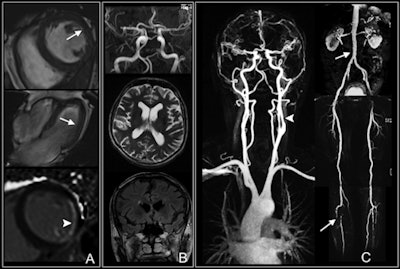

Whole-body MRI shows multiple findings in a 74-year-old man with type 2 diabetes for 21 years. Cardiac images (A) show impaired function with anterolateral hypokinesia (arrows). Late gadolinium-enhanced image (bottom) shows enhancement of anterolateral myocardium (arrowhead) indicative of myocardial infarction. Cerebral images (B) show normal cerebral arteries. Vascular images (C) demonstrate 50% stenosis of left internal carotid artery (arrowhead) and luminal irregularities of the abdomen (upper arrow), thighs, and lower leg with severe atherosclerotic disease and vessel occlusion (lower arrow). Images courtesy of Radiology.The initial study results suggest whole-body MRI can provide "strong prognostic information" about diabetic patients and their potential for a heart attack or stroke, the authors concluded.